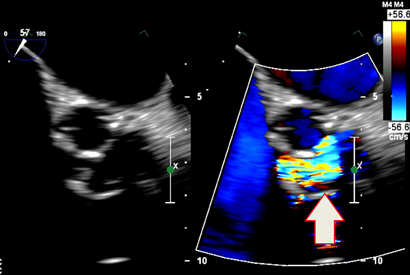

Transthoracic echocardiography showed severe prosthetic valve aortic regurgitation and thickening of the prosthetic valve leaflets with moderate aortic stenosis, with a maximum gradient of 96 mmHg and a mean gradient of 51 mmHg. Transoesophageal echocardiography confirmed severe transvalvular aortic regurgitation and thickened prosthetic valve leaflets, but no defined vegetations were present (Box 1).